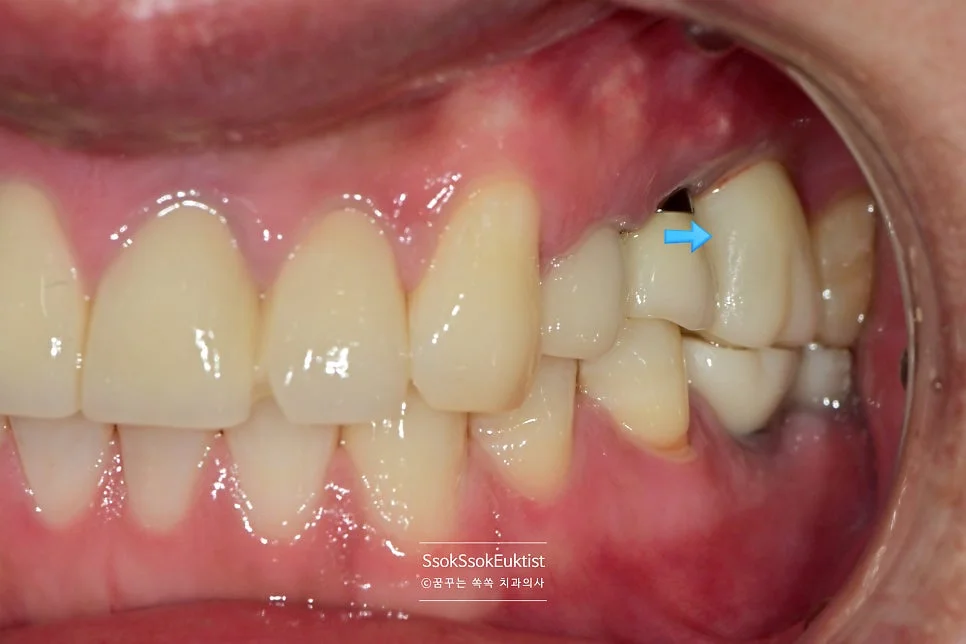

임플란트 식립한 자리 주변이 예쁘게 잇몸으로 아문 것을 볼 수 있습니다.

이제 묻혀 있는 임플란트를 꺼내어 보철물을 연결하면 치료는 마무리됩니다.

- 앞뒤 치아와 가급적 빡빡하게

- 높이는 같게

- 치아가 맞물리는 것은 가운데서 씹을 때 높지 않게

- 좌우로 지글지글 갈 때 걸리지 않게

만들면 좋은 보철물입니다!^^

2번 자리의 잇몸을 보면 처음보다는 훨씬 건강한 잇몸이 된 것을 볼 수 있는데요. 한 달 후 체크 약속에서도

1개월 후 경과 관찰 — 2번 자리 잇몸이 건강하게 자리 잡아가는 모습

건강한 잇몸이 자리 잡아가는 것을 볼 수 있습니다.